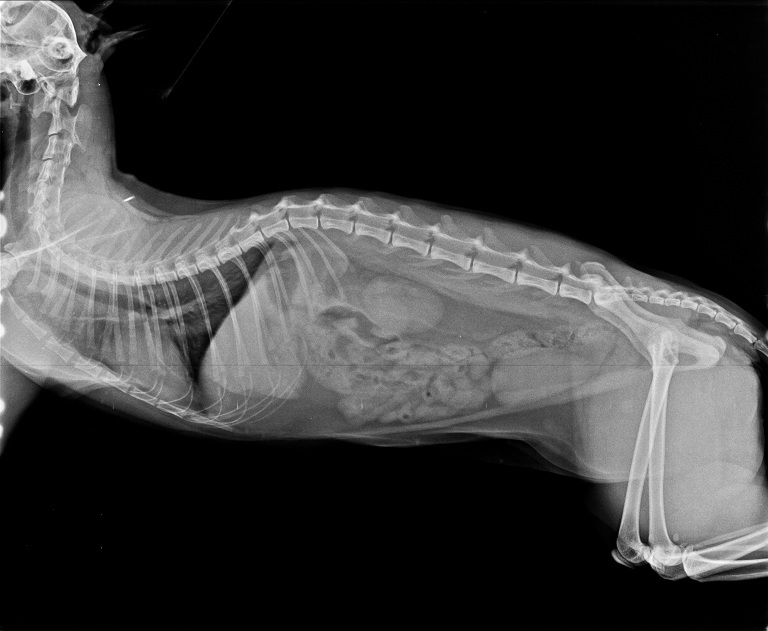

香香在醫院除了做詳細的血液檢查,

也拍了X光照片看清楚香香體內是否有吞入異物,

所幸X光照片並沒有拍到有吞入異物的跡象。